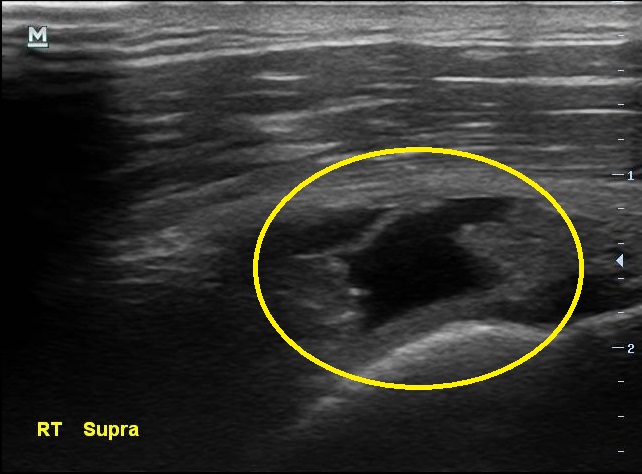

통증이 있지만 운동을 멈추지 않았다는 남자분.... 결과는 생각보다 나빴습니다. 초음파 검사상에서 이두박근의 장두에 염증이 보였고 극상근 힘줄에는 부분파열 소견이 보이고 있었습니다.

초음파 검사 결과 3개월전에 비해 극상근 힘줄의 파열 정도가 더 심해져있습니다.